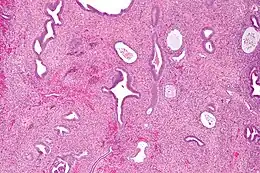

Un polype utérin vu par micrographie.

Un polype endométrial ou polype utérin est une masse dans la paroi interne de l'utérus. Il peut avoir une base large et plate (sessile) ou être attaché à l'utérus par un pédicule allongé (pédiculé). Les polypes pédiculés sont plus fréquents que les sessiles. Leur taille varie de quelques millimètres à plusieurs centimètres. S'il est pédonculé, il peut passer à travers le col de l'utérus et se voir dans le vagin. Le polype est alors accouché par le col. De petits vaisseaux sanguins peuvent se former, en particulier dans les grands polypes. Ces polypes peuvent être à l'origine de ménométrorragies.